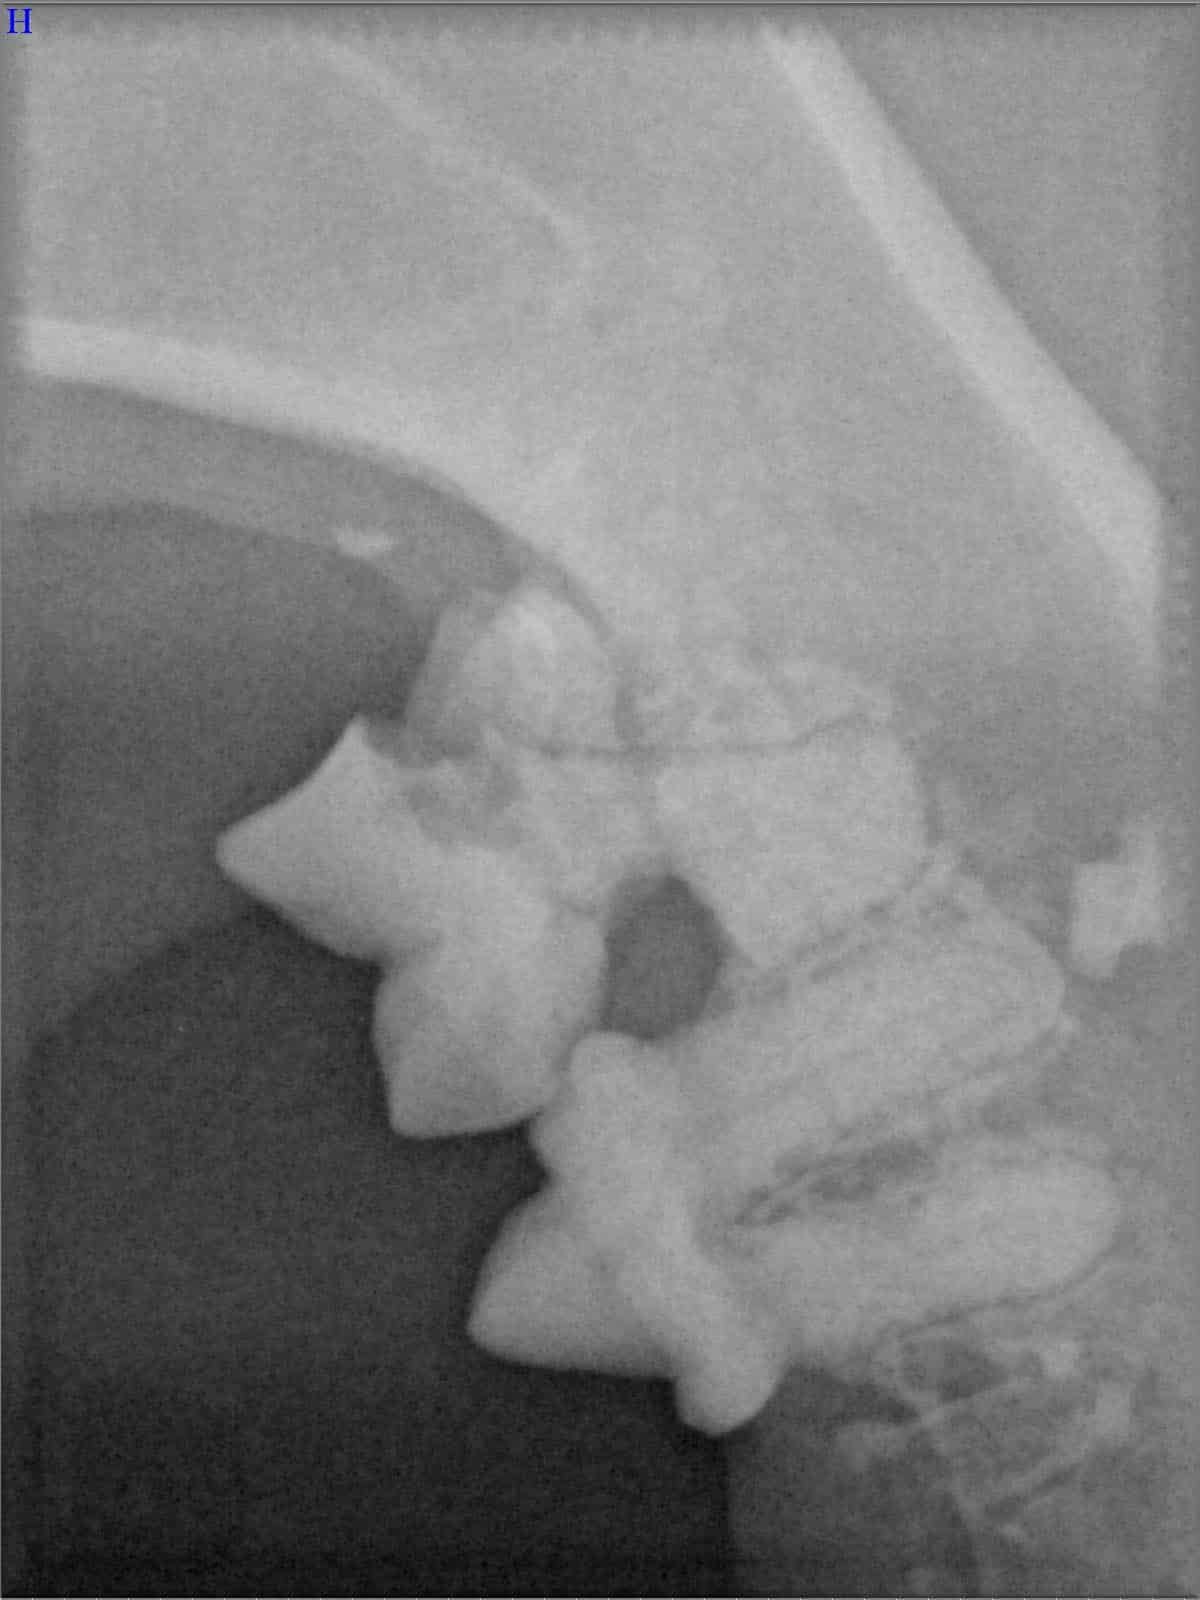

Röntgenbilder

(Fraktur + Wurzelentzündung durch Zahnstein)